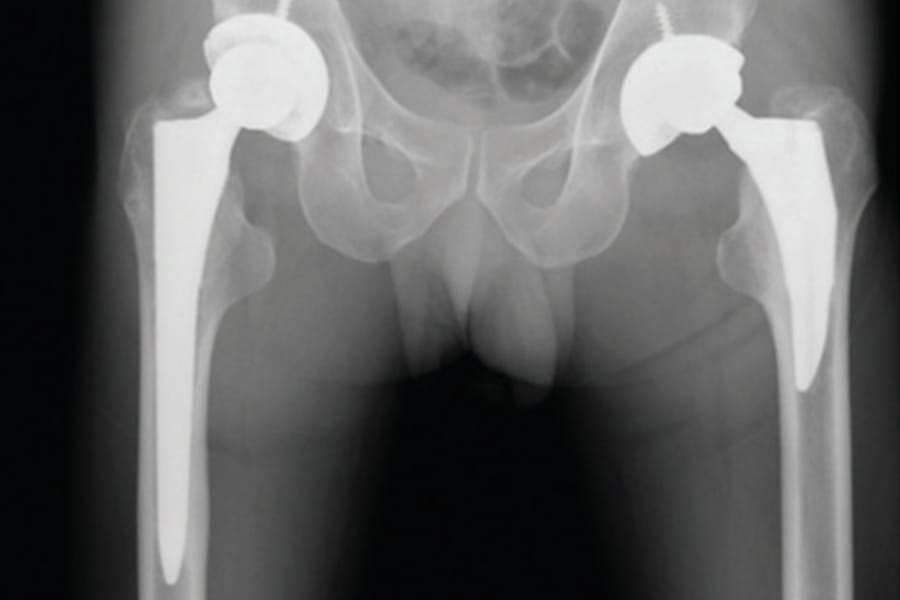

This month, we are honored to feature an interview with Professor Eleftherios Tsiridis, reflecting on a career defined by scientific curiosity and leadership in European orthopedics. The issue broadly examines the evolution of hip arthroplasty, offering critical updates on the biomechanics of Dual Mobility systems and the long-term efficacy of third-generation highly cross-linked polyethylene (XLPE).

Clinical articles in this edition address the pursuit of anatomical restoration, comparing short-stem versus standard prostheses and detailing the piriformis-preserving STAR approach. We also explore the complex management of Developmental Dysplasia of the Hip (DDH) and evaluate advanced solutions for revision surgery, including the BioBall® modular adapter and custom 3D-printed acetabular implants for severe bone defects.